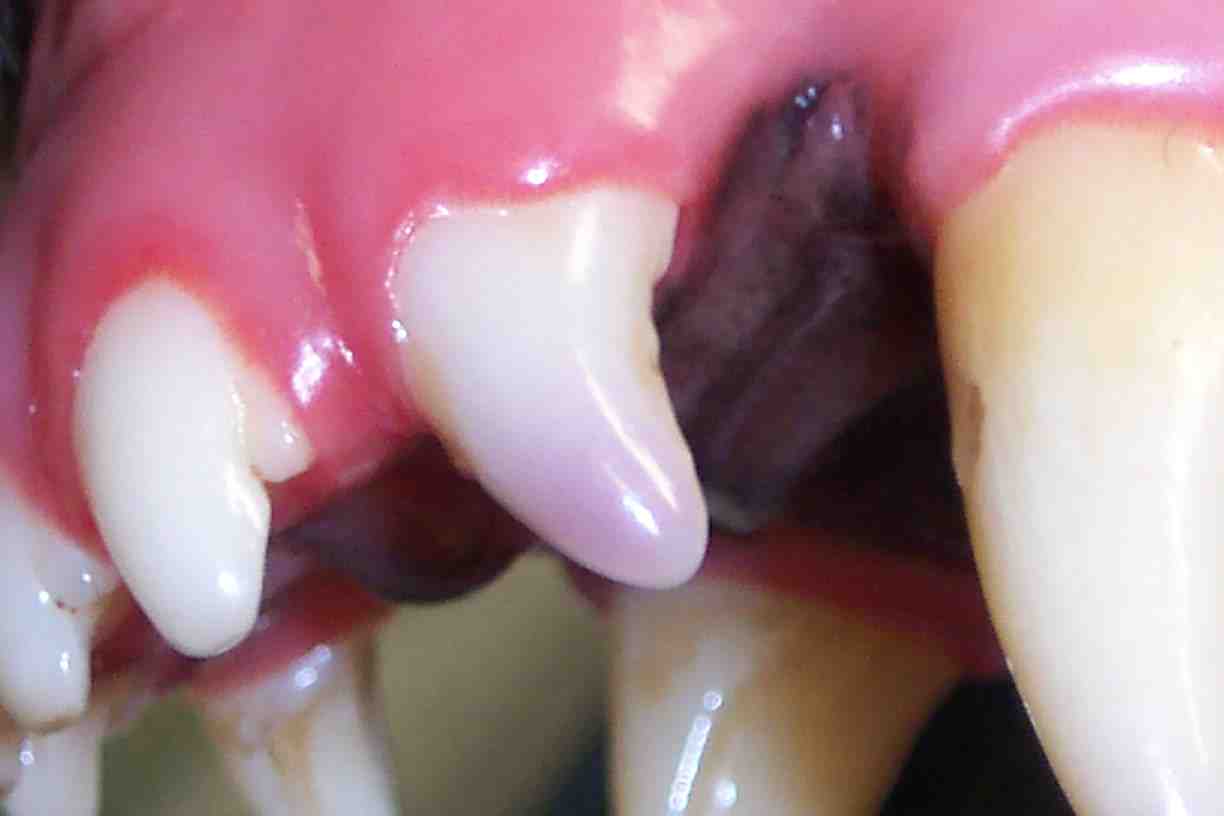

These teeth often appear discolored (pink, purple-to-gray). Similar to a skin bruise, the color change is a result of hemorrhage and the bursting of red blood cells within the tooth. Because the pulp is enclosed within a hard rigid chamber, any inflammation can rapidly increase inner pressure and restrict blood flow. Eventually, pulpitis most often progresses to pulp and tooth death.

Usually pulpitis can be determined visually. If the tooth appears intrinsically discolored (a color change from within, not on the exterior), then pulpitis has occurred. In addition to a complete oral examination, dental x-rays may be obtained to help assess the tooth status. Unfortunately, in 42% of discolored teeth, x-rays appear normal. Likewise humans experiencing discomfort due to pulpitis do not always show changes on x-rays.

The canine tooth with pulpitis (above left) was treated with root canal therapy then bleaching. The after photo, on the right, shows the same dog with his pearly whites back again.